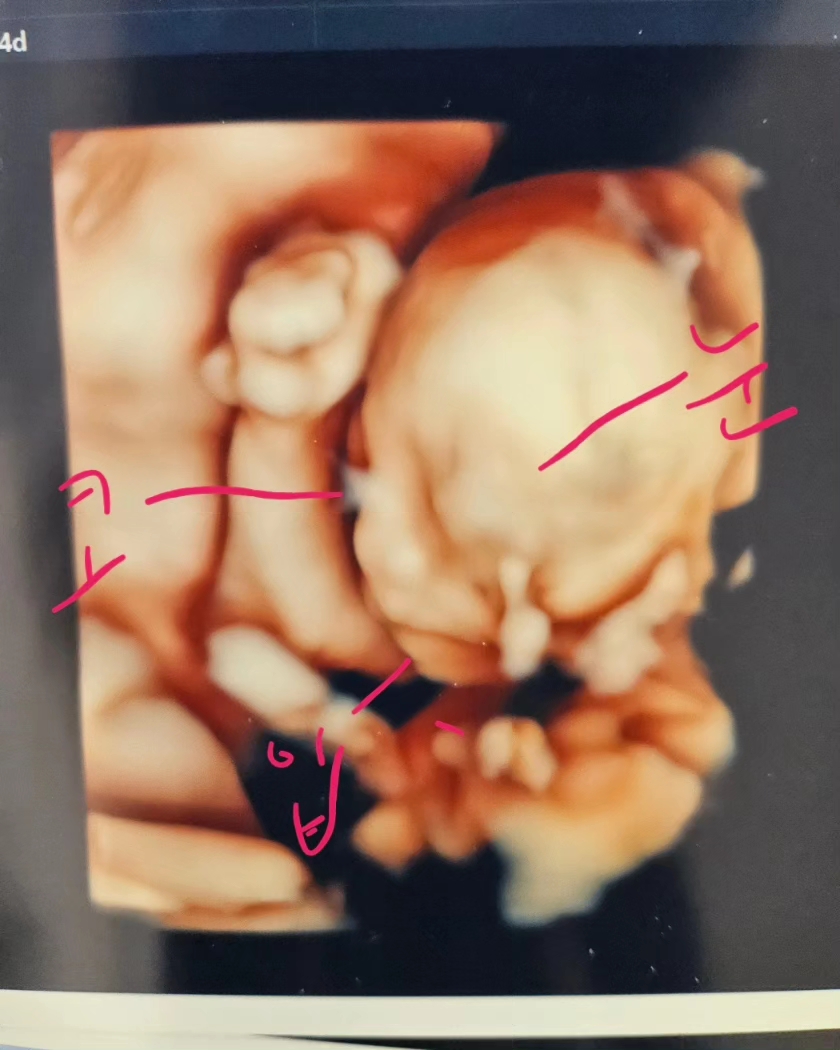

귀여운 땡글이 입초 자랑이용💕

임신중 디스크가 터져서 ... ㅠㅠㅠ 고대에 입원중인데 수술도 못하도 무통만 맞으면서 아픈거 참아가며 잇지만 ㅠㅠ 이와중에 산부인과 교수님이 땡글이는 잘잇다며 입초 보여주셔서 ㅠㅠ 위안이 됫다눈 ㅠㅠ 엄청아프지만 저 사진 보면서 힘내고 잇는데 ㅎㅎ저희 땡글이 너무 귀엽죠 ?!😍😍

주먹을 꽉쥐고 엄마 화이팅! 하고있네요 디스크가. 터지다니 ㅠㅠㅠ 어후 너무 힘드시겠어요ㅠㅠ

ㅎㅎ 그러게요!!진짜 주먹쥐고 화이팅해주고 잇네요 ㅎㅎㅎㅎ 좀 무리좀햇더니 허리다 훅 ㅠㅠ 땡추마마님은 무리하지마세용😭😭